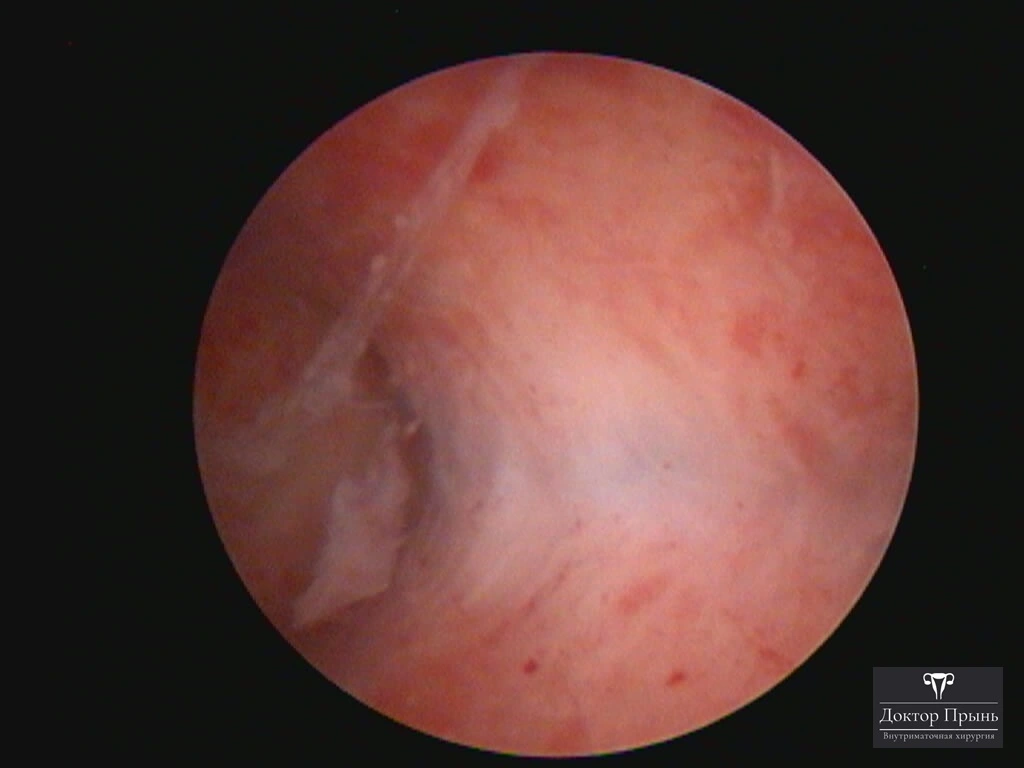

Фотогалерея

Синехии, рассечённые Прынь Д.В.